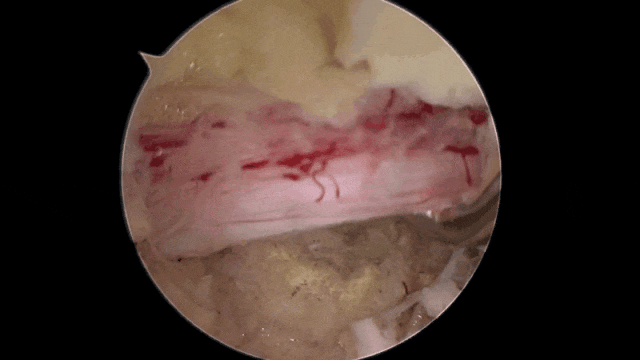

面对小张的焦虑和不安,汪洋主任对他的影像学片子进行了讨论,他发现由于椎间盘突出的位置特殊,要想摘除突出的髓核就首先避开对神经造成较大的损伤和干扰,因为,UBE(单侧双通道内镜技术)就成了微创治疗的首选

图片

UBE微创术中

进入手术室,小张很快进入了麻醉状态,术中完全摘除突出的髓核,神经根压迫解除。术后症状消失,24小时后即可下地行走,小张对手术效果非常满意。